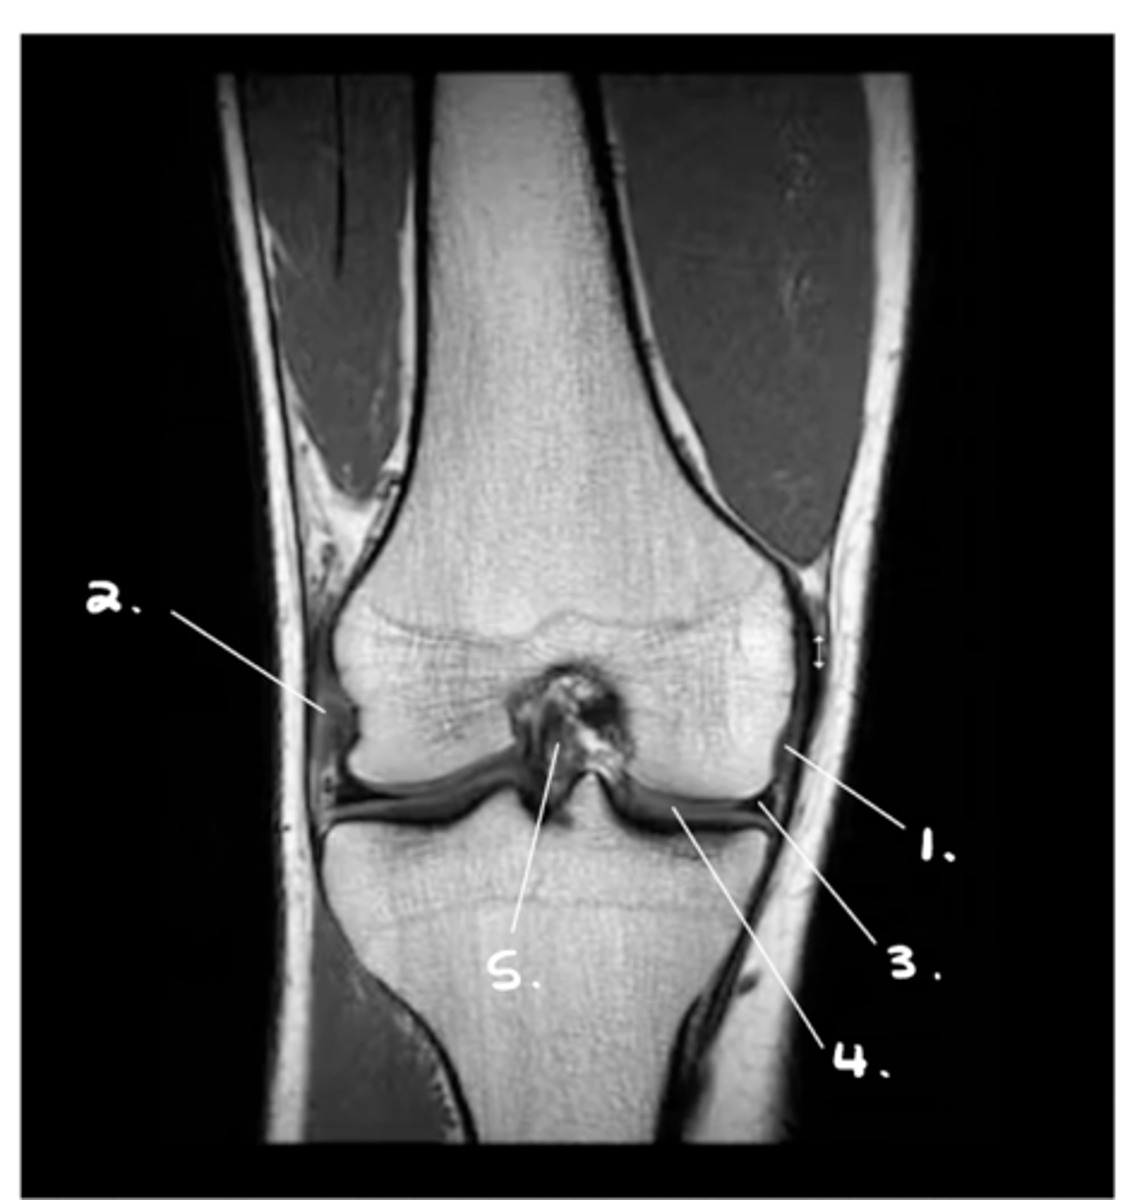

1. MCL

2. LCL

3. Medial meniscus

4. Hyaline cartilage of tibia & femur

5. ACL

Label 1-5.

Grade III MCL tear

Define the pathology.

GOTCHA!! This is a NORMAL LCL!!

Torn LCL

Define the pathology. (#1 is just pointing to the meniscus)